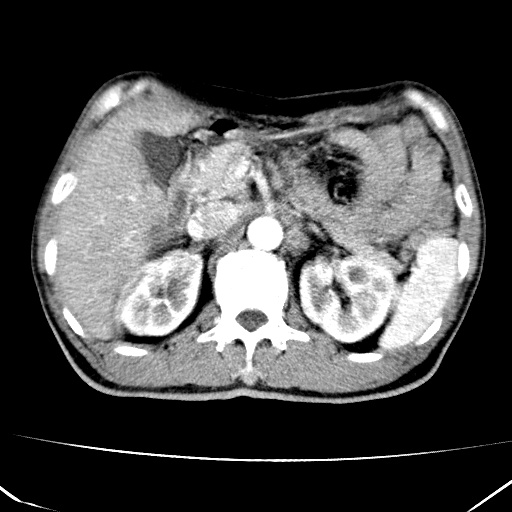

标题: CT17975:请求会诊。男、57岁。上腹部胀痛2天。临床诊断:糜 [打印本页]

标题: CT17975:请求会诊。男、57岁。上腹部胀痛2天。临床诊断:糜

肝脏多发类圆形低密度影,考虑肝脏转移瘤,肝胃韧带一淋巴结肿大,原发?胃癌?

考虑胃癌并肝脏及腹膜后淋巴结转移;不排除淋巴瘤。

肝内转移瘤,腹腔及腹膜后淋巴结转移。